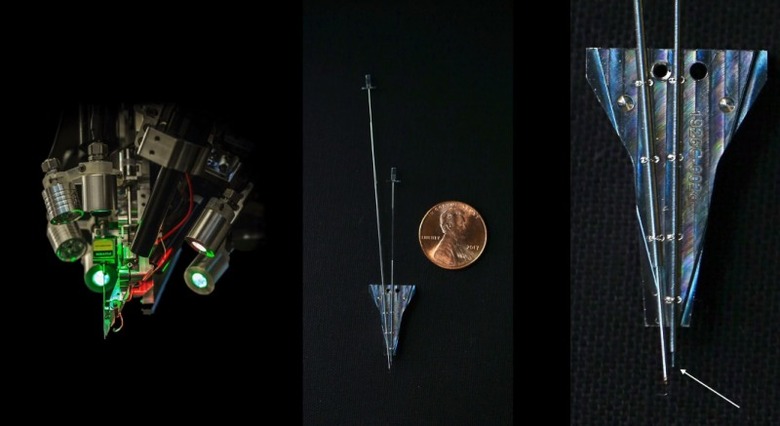

One big reveal is that it "hopes" to begin working on human subjects as soon as the second quarter of next year. In the picture above, that was shown during the presentation, that small protrusion at the bottom right with the arrow pointing to it, is the size of the thread that it actually hopes to implant.

According to the article, its bundles of flexible threads are about one quarter the diameter of a human hair, implanted using needles to avoid blood vessels on the brain's surface. Then the embedded sensors capture information and send it to a receiver (the chip above) on the surface of the skull. From there it transmits wirelessly — Elon Musk said it could Bluetooth the information to your skull. Right now implantation requires drilling holes, but researchers hope in the future they can use lasers to avoid "unpleasant" vibration.

Neuralink president Max Hodak went on to explain why it's embedding sensors directly into the brain, near but not in neurons. Simply, it's the only way to send and receive the information necessary, from "spikes" of activity. A neurosurgeon is also part of the presentation, showing off some videos of the implantation technology, and how its robot can install thousands of wires directly into the brain while avoiding tissue damage and bleeding. Eventually, they'd like to do it without shaving the patient's head, although he acknowledged that the first operations will be more like current deep brain implants.